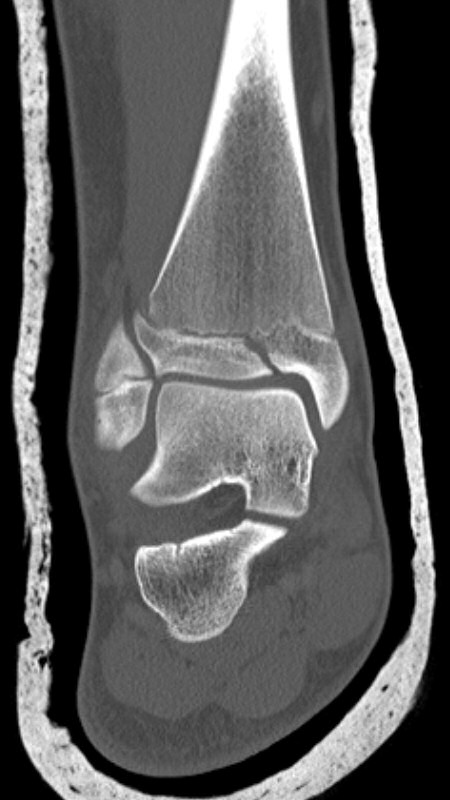

Exempel på triplansfraktur hos nästan färdigvuxet barn

På akutmottagning

Gör DT för att avgöra frakturtyp och felställning.

Triplanfraktur = triplansfraktur = treplansfraktur: fraktur i distala tibia som engagerar både metafys, fys och epifys. Kan vara 2, 3 eller 4 fragment. I 50 % av fallen är även fibula frakturerad [3].